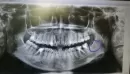

У меня на месте 8-ки или дальше неё есть твёрдое образование. Будто лезет зуб внутрь, в сторону языка, но зубы мудрости у меня уже выросли и их удалили. Раньше слева было просто твердое. А на днях начала болеть вся левая десна, а в том месте как острие появилось. При нажатии болит, но не сильно. И с правой стороны тоже есть чуть припухлость твердая, но гораздо меньше. Еще с апреля прошлого года у меня зубы стали сами сильно смещаться и даже чуть поворачиваться.

На этом снимке не определяется ничего необычного в обведенной области. Скученность могли вызвать зачатки восьмых зубов, патология окклюзии, вредные привычки. Вам необходимо обратиться к стоматологу-ортодонту для диагностики.